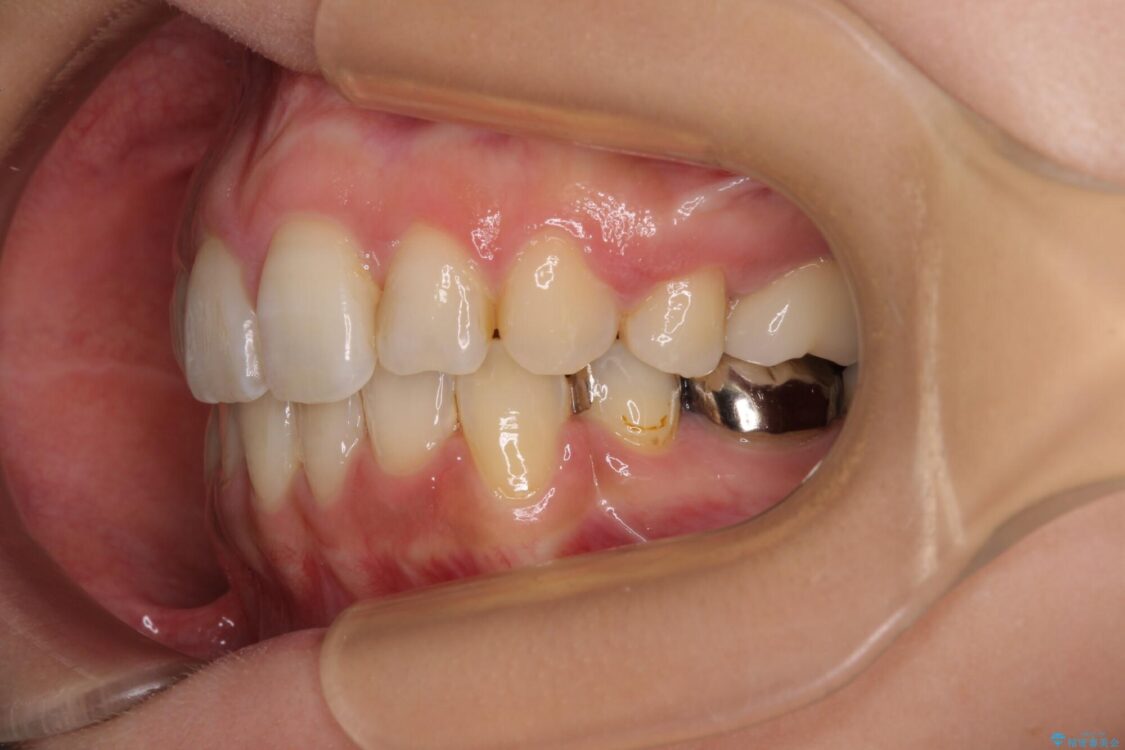

治療前

• デコボコと口元の突出感 ハーフリンガルでの抜歯矯正 治療前画像